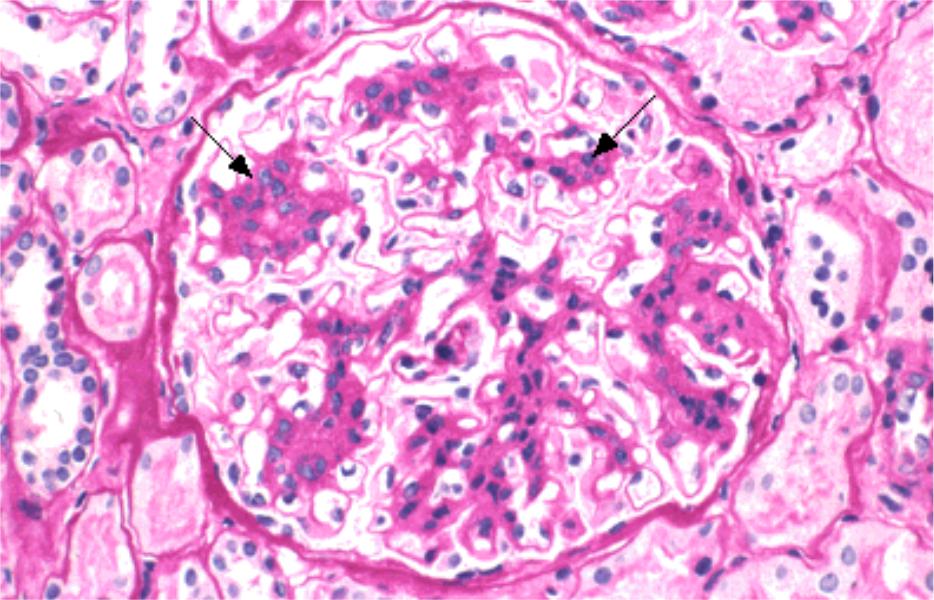

Механизм остро го диффузного гломерулонефрита